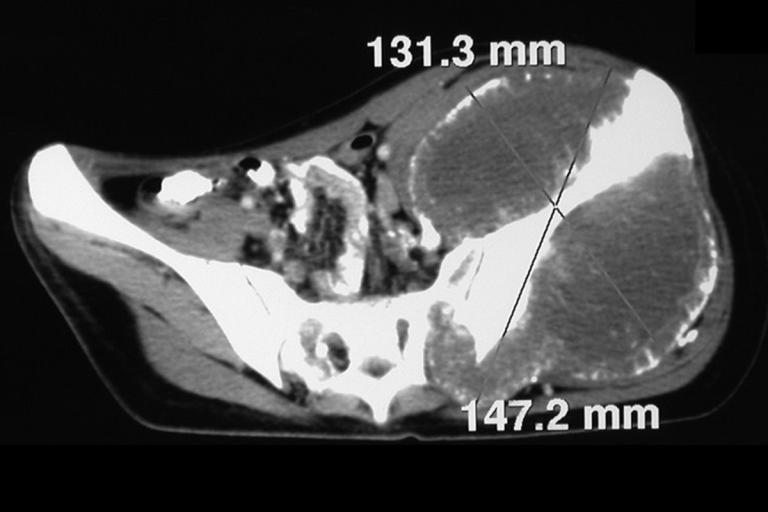

Tomografia Computadorizada (TC)

- Axial e coronal com densidade para osso e tecidos moles: Revelaram grande tumor acometendo o ilíaco esquerdo.